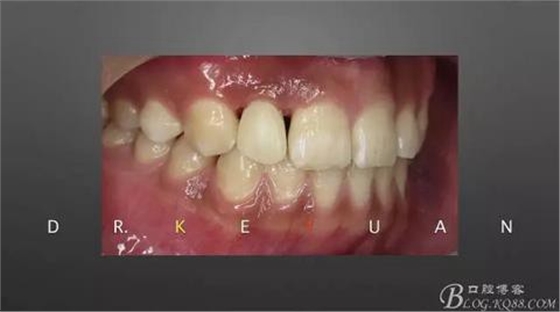

10、復(fù)診試戴最終修復(fù)體(又爭取了2周的時(shí)間,再加上技師對(duì)最終修復(fù)體鄰接關(guān)系的設(shè)計(jì),牙齦恢復(fù)效果明顯)

11、牙齦狀況對(duì)比(有時(shí)候你把患者約的時(shí)間太長,他可能會(huì)不理解你,約著約著就再也約不過來了,有些時(shí)候患者的修復(fù)熱情和臨床的治療程序可能成反比,我們要做金玉其外、金玉其中的修復(fù),實(shí)難取舍)

12、粘接后即刻(齦緣的高度略有差異,這應(yīng)該可以說明冠延長術(shù)和正畸牽引的效果差異)

13、術(shù)前術(shù)后對(duì)比

14、術(shù)后微笑照